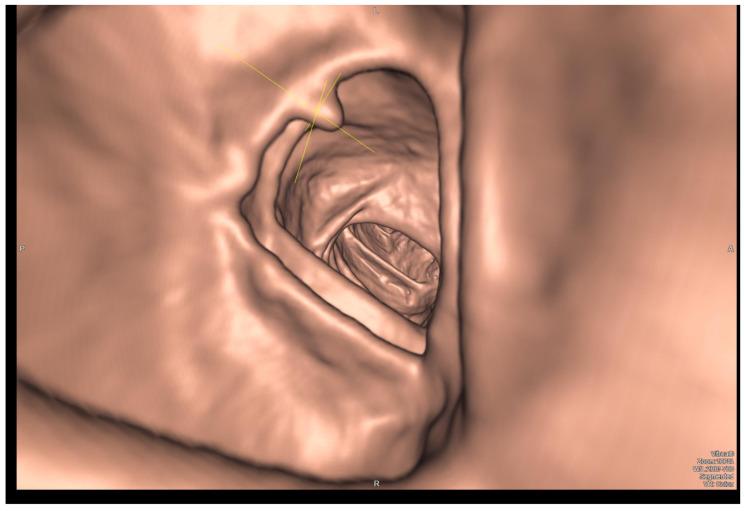

Rectal cancer (RC) is a prevalent malignancy with significant morbidity and mortality rates. The accurate staging of RC is crucial for optimal treatment planning and patient outcomes. This review aims to summarize the current literature on imaging and metabolic diagnostic methods used in the stage assessment of RC. Various imaging modalities play a pivotal role in the initial evaluation and staging of RC. These include magnetic resonance imaging (MRI), computed tomography (CT), and endorectal ultrasound (ERUS). MRI has emerged as the gold standard for local staging due to its superior soft tissue resolution and ability to assess tumor invasion depth, lymph node involvement, and the presence of extramural vascular invasion. CT imaging provides valuable information about distant metastases and helps determine the feasibility of surgical resection. ERUS aids in assessing tumor depth, perirectal lymph nodes, and sphincter involvement. Understanding the strengths and limitations of each diagnostic modality is essential for accurate staging and treatment decisions in RC. Furthermore, the integration of multiple imaging and metabolic methods, such as PET/CT or PET/MRI, can enhance diagnostic accuracy and provide valuable prognostic information. Thus, a literature review was conducted to investigate and assess the effectiveness and accuracy of diagnostic methods, both imaging and metabolic, in the stage assessment of RC.

直肠癌(RC)是一种常见的恶性肿瘤,发病率和死亡率都很高。准确的直肠癌分期对于优化治疗方案和患者预后至关重要。本综述旨在总结目前关于直肠癌分期评估中使用的影像学和代谢诊断方法的文献。各种影像学检查在直肠癌的初始评估和分期中起着关键作用。这些检查包括磁共振成像(MRI)、计算机断层扫描(CT)和直肠内超声(ERUS)。由于MRI具有卓越的软组织分辨率以及评估肿瘤浸润深度、淋巴结受累情况和壁外血管侵犯的能力,它已成为局部分期的金标准。CT成像提供了有关远处转移的有价值信息,并有助于确定手术切除的可行性。ERUS有助于评估肿瘤深度、直肠周围淋巴结和括约肌受累情况。了解每种诊断方法的优缺点对于直肠癌的准确分期和治疗决策至关重要。此外,整合多种影像学和代谢方法,如PET/CT或PET/MRI,可以提高诊断准确性并提供有价值的预后信息。因此,我们进行了一项文献综述,以研究和评估影像学和代谢诊断方法在直肠癌分期评估中的有效性和准确性。